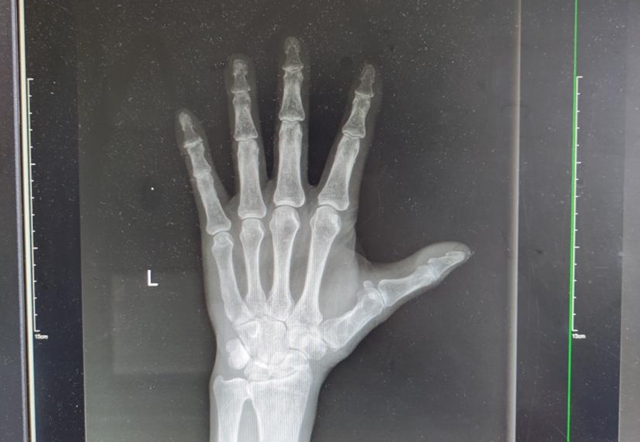

出院1年半后患者功能恢复情况

半年骨折完全愈合